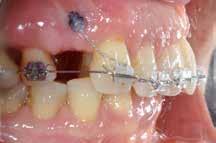

Der planlægges alignerbehandling af begge kæber med intrusion af 1+1 og 2,1-1,2, nivellering af trangstilling UK med interproksimal reduktion (IPR) (Fig. 2 A, B) og senere IPR OK for reduktion af dark triangles mellem incisiverne efter nivellering. Patienten instrueres i at benytte alignere 20-22 timer/ dag med alignerskift hver 7. dag, og patienten ses hver 3.-8. uge under forløbet. Den første alignerserie består af 16 alignere for nivellering OK/UK og IPR i UK (Fig. 2). Efter denne serie planlægges IPR mellem incisiverne i OK for reduktion af dark triangles (Fig. 3) samt yderligere intrusion af OK og UK-fronten i 12 refinement-alignere. Patienten udviser god kooperation og er meget tilfreds med alignerapparaturet, som er mindre synligt end det faste apparatur (Fig. 4).

Behandlingen afsluttes med yderligere refinement-alignere for finindstilling af okklusionen, og efter 11 måneders ortodontisk behandling er der opnået normale relationer i alle tre